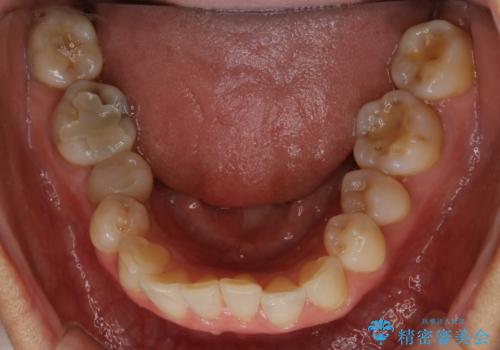

前歯の反対咬合、奥に引っ込んでしまっている歯をインビザラインで治療する

上の前歯の反対咬合があり、治療の途中で下の前歯を乗り越える必要があります。

インビザラインでこのような症例を行う場合、乗り越えるのに必要な期間が長くなります。

その為、奥歯で咬みにくい期間が長くなってしまいやすいです。